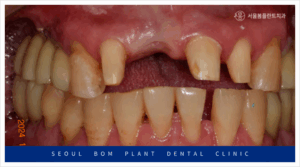

위턱 오른쪽 앞니(#11)의 경우

환자분과 충분한 상담을 통해

양옆의 치아를 이용한

브릿지 보철물을

진행하기로 계획하였는데요.

기존 임플란트가 빠지고

잇몸뼈가 소실이 심한 상태라

잇몸뼈가 어느 정도 찰 때까지

충분한 시간을 가지고

진행하기로 하였으며,

심미성이 중요한 앞니이다 보니

일상생활에 있어 불편감을

덜어드리기 위해

wire temporary 제작하여

사용하실 수 있도록

도와드리기로 하였습니다.